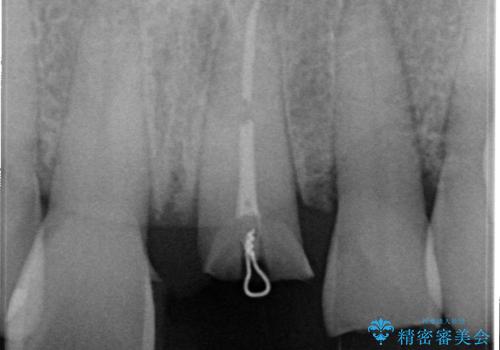

根管治療をした上で歯を引っ張りだして(エクストリュージョン)、その後、骨外科にて歯周組織を整えた上で、かぶせものを入れていく治療計画をたてました。

とても治療に対しての意識が高い方で、最初のころは歯磨きもあまりできていませんでしたが、衛生士さんの指導もあり、治療を進めるうちにプラークコントロールも改善していました。

歯を引っ張りあげたり、手術をしたあとの治り待ちをしたり、治療に時間がかかる方法ではありましたが、抜かずにその歯を使うことができたことで、患者さんにはとても満足していただけています。